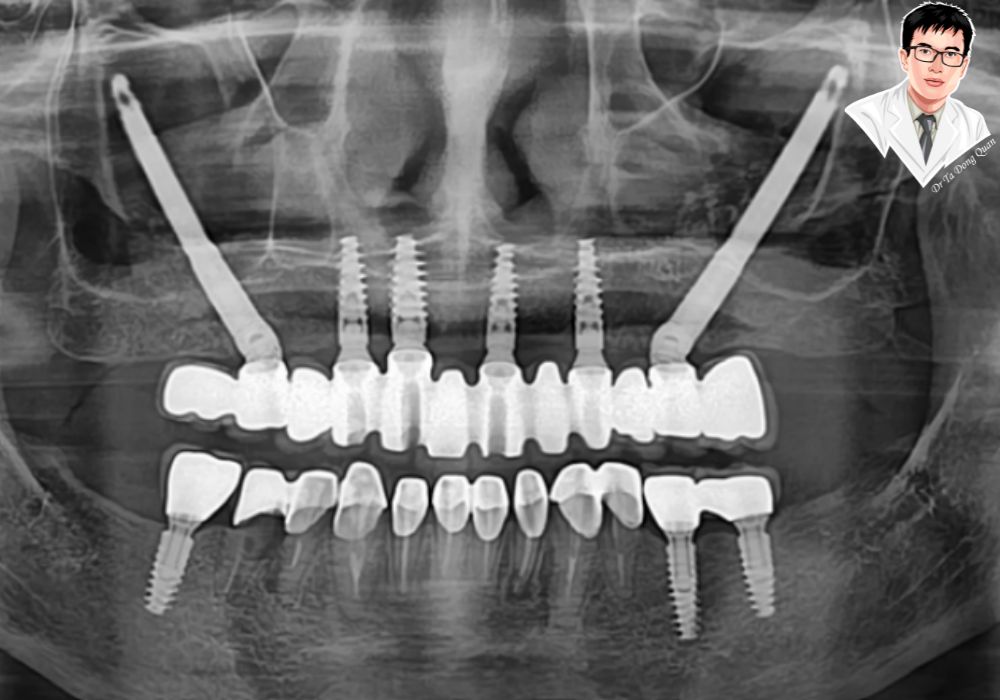

Hình minh họa sự tích hợp giữa trụ implant và xương hàm trong quá trình phục hồi sau cấy ghép toàn hàm.

Phục hình răng toàn hàm bằng implant Zygoma, cấy nghiêng và dài để bám vào xương gò má.